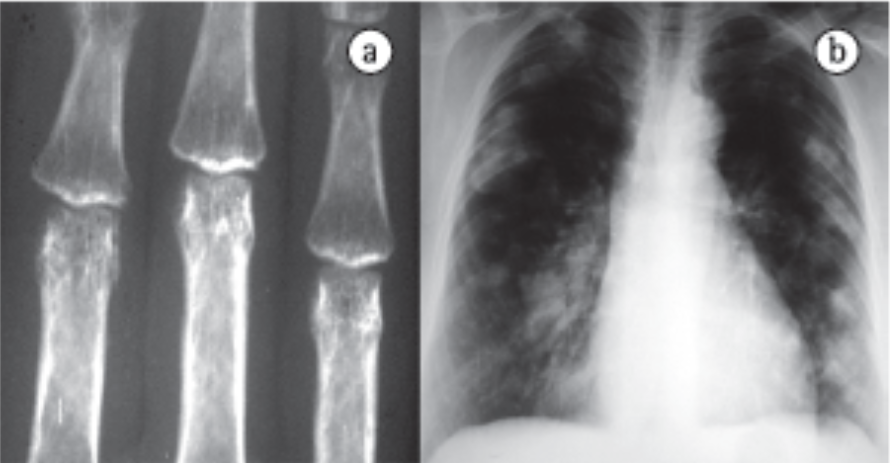

Síndrome de Caplan (Pneumoconiose Reumatoide)

Uma manifestação rara onde ocorre a combinação de Pneumoconiose (Silicose ou Carvão) + Artrite Reumatoide.

- Imagem: Nódulos pulmonares periféricos, múltiplos, de evolução rápida e grandes (1 a 5 cm), podendo cavitar.